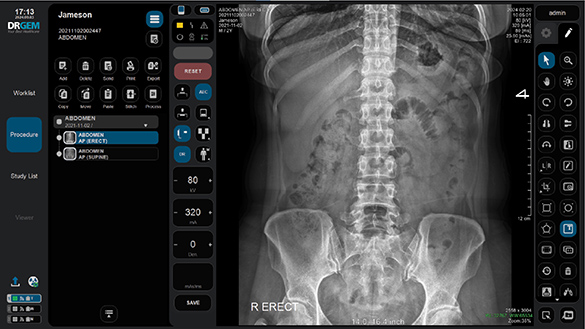

Patient Registration & X-ray Preparation

Seamless Patient Setup

Register a new patient or select an existing case directly from the worklist to begin the training workflow smoothly and efficiently.

Guided Positioning and Exposure Setup

RadTrainer supports real clinical preparation by guiding patient positioning and exposure setup. It uses an extensive high-resolution image library covering 23 body parts and 337 positioning scenarios, based on real images used in general hospitals for realistic training and image review.